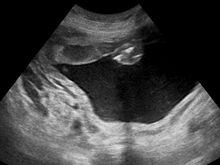

Polyhydramnios (polyhydramnion, hydramnios, polyhydramnios) is a medical condition describing an excess of amniotic fluid in the amniotic sac. It is seen in about 1% of pregnancies.[1][2][3] It is typically diagnosed when the amniotic fluid index (AFI) is greater than 24 cm.[4][5] There are two clinical varieties of polyhydramnios: